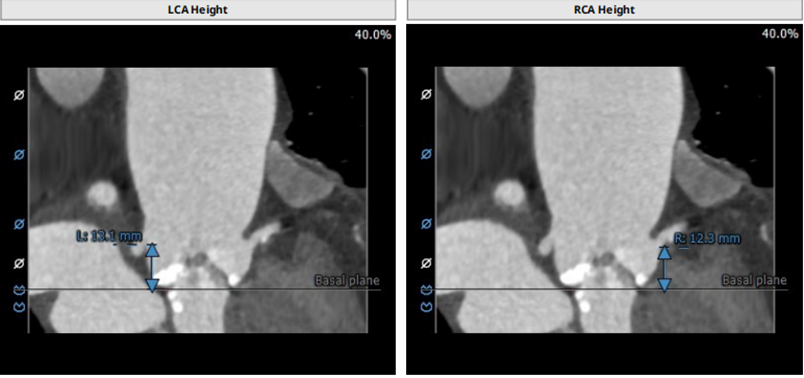

主动脉根部:TYPE0型二叶瓣,瓣叶增厚,中度钙化,钙化主要集中在瓣叶上,瓣环及流出道可见钙化延伸,右冠高度约12.3mm,左冠高度约 13.1mm,法式窦结构较小,STJ高度约19.5mm,直径约29.7mm,升主动脉可见增宽,最宽处约43.5mm,心脏角度呈横位,约 76°,建议备Snare,心肌肥厚,左室较小(自杀左心室),存在循环奔溃风险,建议术前及术中注意补液,工作体位:CRA:29°。不建议预扩,标准位释放。入路:主动脉弓部走行迂曲,角度约83°,无名动脉、左颈动脉、左锁骨下动脉起源自主动脉弓部,未见发育变异,降主动脉走形较平直, 管腔未见狭窄,双侧股动脉走形较平直,管腔未见狭窄,左侧股动脉分叉在股骨头下缘处,右侧股动脉分叉在股骨头下1/3处。